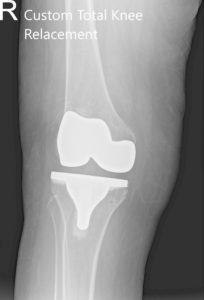

Radiografía postoperatoria que muestra AP y vistas laterales de la articulación de la rodilla derecha e izquierda.